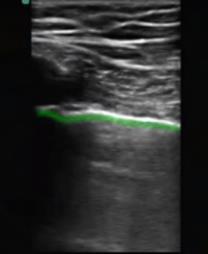

Bild: Lunge, markierte Pleura visceralis

Markierter Bereich: Pleura visceralis